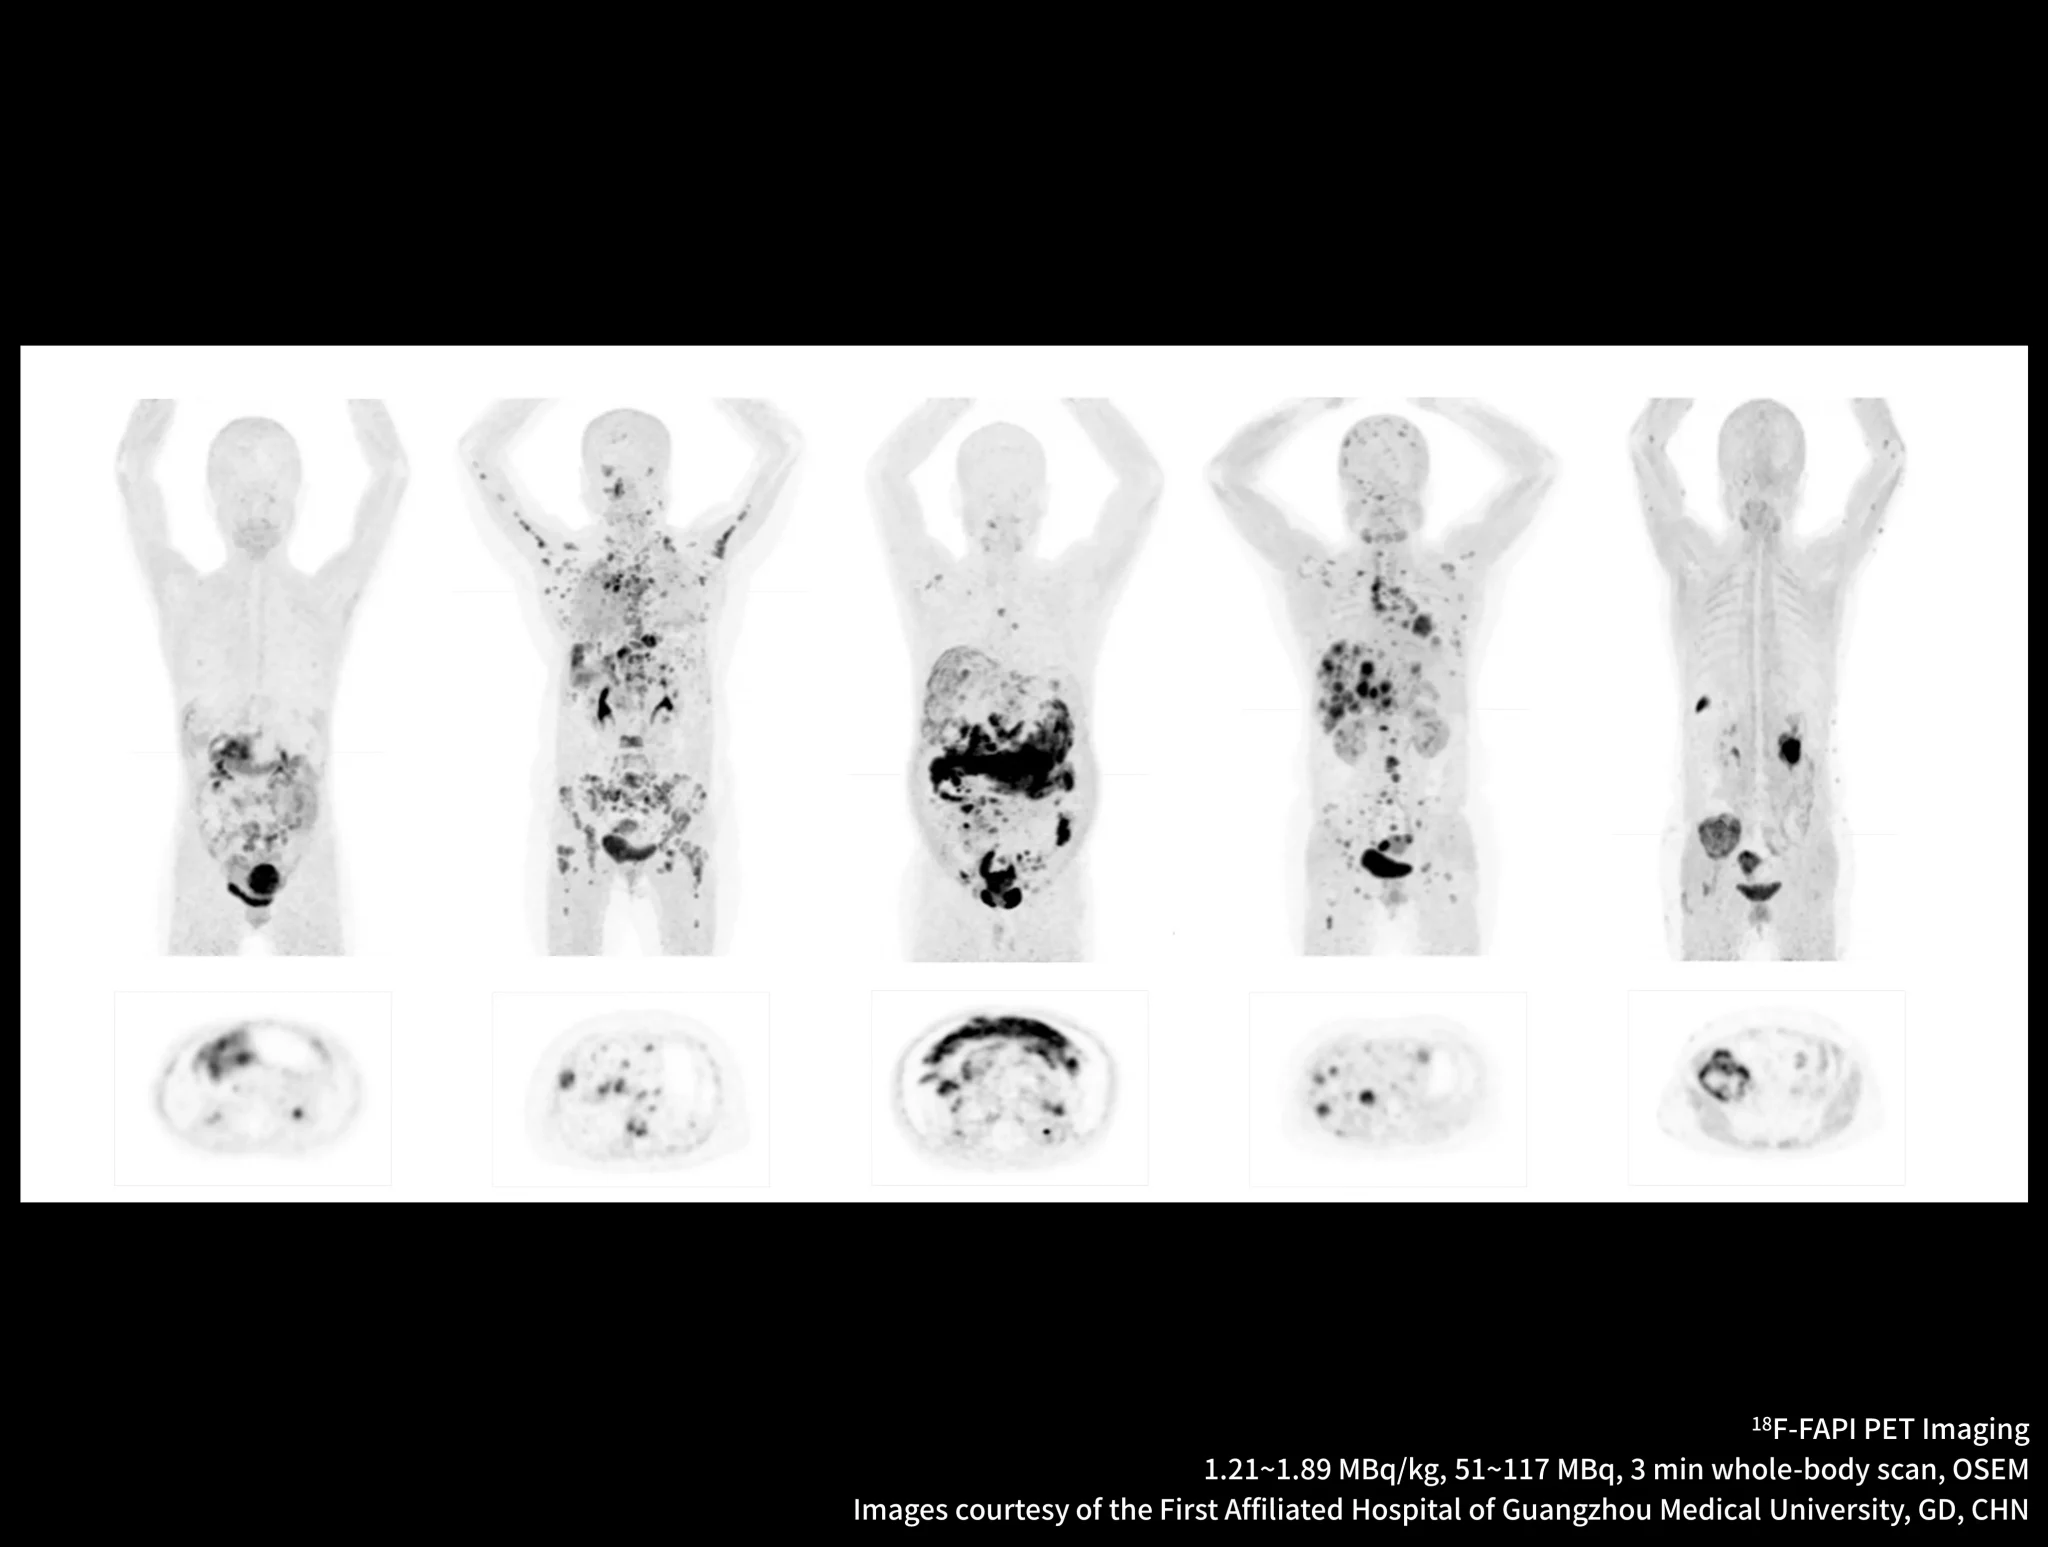

New-Tracer Imaging

Click on different tracers to see the images.